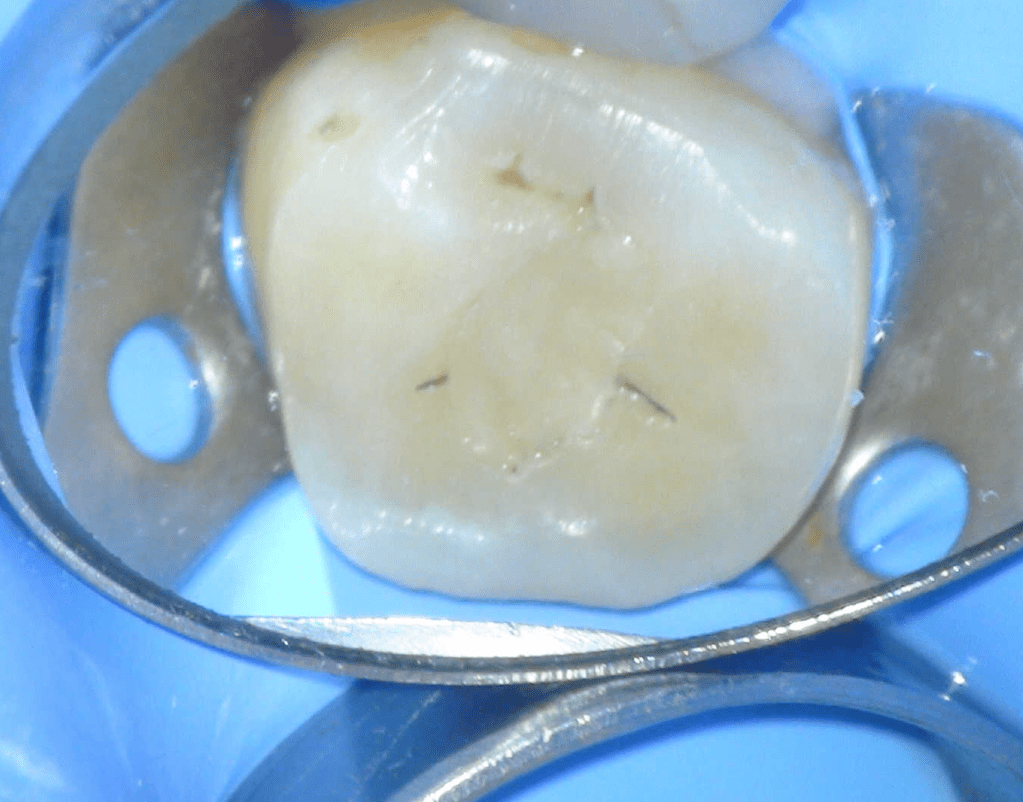

Fisura, remoción amalgama para explorar